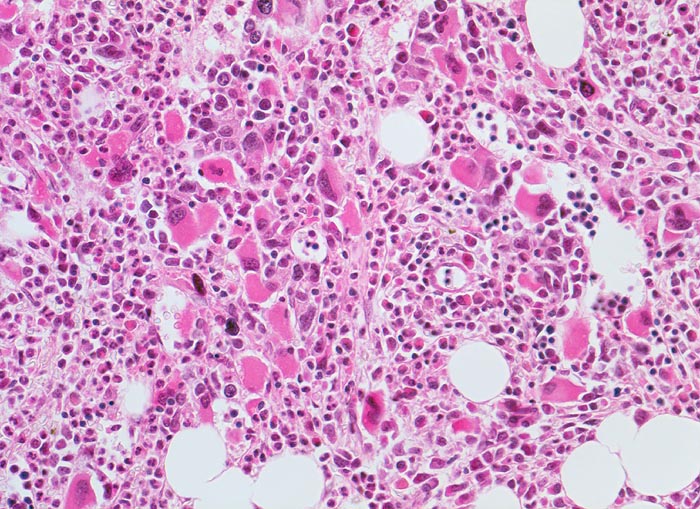

Die Erkrankung ist charakterisiert durch Knochenmarkfibrose, Hepato-Splenomegalie und extramedulläre Blutbildung. Diese findet sich am häufigsten in Leber und Milz, seltener in Lymphknoten, Nieren, Nebennieren, Dura mater, Gastrointestinaltrakt, Lunge, Mamma oder Haut. Blut und Knochenmark sind immer involviert. Die Krankheit entwickelt sich über ein initiales präfibrotisches Stadium mit hyperzellulärem Knochenmark zum fibrotischem Stadium (vorliegendes Präparat). Das fibrotische Stadium ist gekennzeichnet durch eine Vermehrung von Reticulin- und/oder Kollagenfasern und oft einer Knochenneubildung (=Osteomyelosklerose). Die Zellularität des Knochenmarks ist dann vermindert und dilatierte Marksinus enthalten intraluminale Blutbildungsherde. Es besteht eine auffallende Proliferation von Gruppen bildenden atypischen Megakaryozyten.

• Vermehrung von atypischen, in Gruppen liegenden Megakaryozyten mit abnorm lobulierten Kernen.

• Nacktkernige (zytoplasmaarme) und vergrösserte Megakaryozyten.

• Hyperplastische ausreifende Myelopoese.

• Hypoplastische Erythropoese.